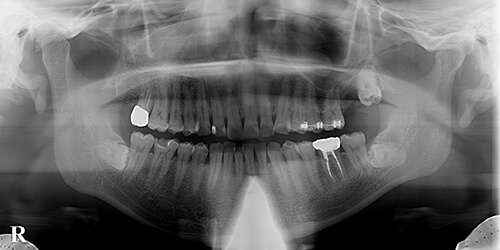

【治療中】

左上7(第2大臼歯)を抜歯すると、その下の8(親知らず)が目視できました。

左上456(第1小臼歯、第2小臼歯、第1大臼歯)を固定源として、止血後に8(親知らず)にも矯正器具を取り付け、矯正的挺出を試みました。